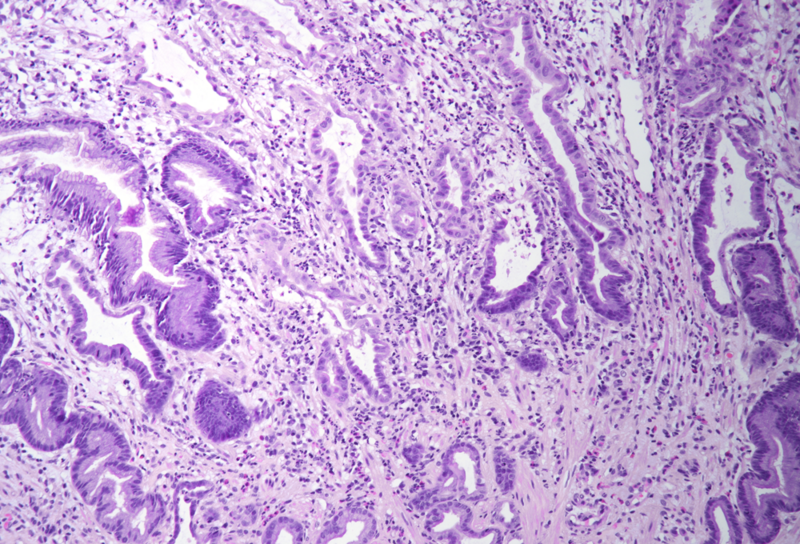

Gastric biopsies from a 68-year-old male with history of lung cancer.

Immune checkpoint inhibitor associated gastritis.

Histology showed an extremely altered gastric mucosa, with architectural distortion by glandular atrophy, degenerative epithelial changes, erosions and an expanded oedematous lamina propria (PANEL A-C). On higher magnification, the lamina propria contained a mixed inflammatory infiltrate, characterized by lymphocytes, plasma cells, eosinophils and neutrophils, focally with abscess formation. We observed withering glands lined by flattened eosinophilic epithelium, occasionally containing apoptotic debris (PANEL D-E); in other areas, little atrophic neuroendocrine nests were found (PANEL F). In summary, there was a severe acute inflammation and signs of acute epithelial injury highly suggestive of a drug-induced gastritis, consistent with injury due to pembrolizumab.